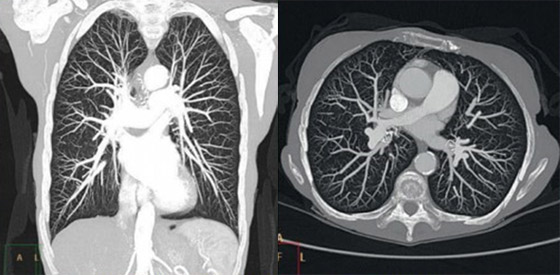

Mit einem SmartPath Upgrade profitieren Sie von unserer fortschrittlichen Rekonstruktionstechnologie IMR (Iterative Modellbasierte Rekonstruktion).

IMR bietet praktisch rauschfreie Bilder in Verbindung mit einer überragenden Niedrigkontrastauflösung und dies mit einer erheblich geringeren Strahlendosis[1]. Bei den meisten Referenzprotokollen beträgt die Rekonstruktionszeit weniger als 3 Minuten*.

* Erfordert IMR Platinum: IMR Platinum bietet als zusätzlichen Vorteil die Rekonstruktion von getriggerten Akquisitionen (EKG- und pulmonal-getriggert) – IMR Cardiac